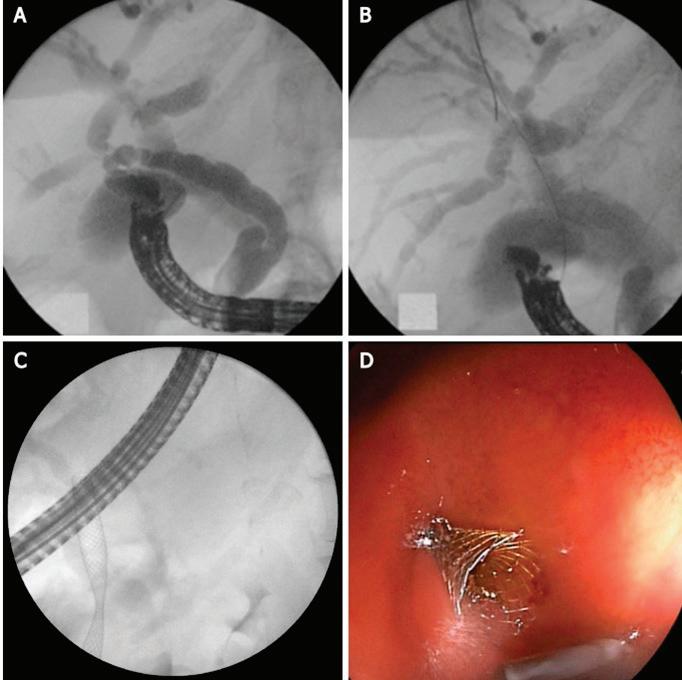

на СА19-9 и карциноембрионален антиген (СЕА) се прилага при пациенти със сус пектен злокачествен процес, като спомага за диагностиката и проследяването му, въпреки че не са специфични маркери за билиарна ма лигненост. При менажирането на такъв тип стенози от из ключителна важност е предварителното ста диране на пациента с образни методи – УЗ, КТ Фиг. 1 Холангиограма на пост оперативна стеноза след холецистектомия Фиг. 2 Холангиоскопски образ при стеноза на анасто мозата след чернодроб на трансплантация чини,

с контраст, магнитно-резонансна хо лангиопанкреатография – неинвaзи вен метод, който не само локализира интрахепаталните жлъчни стриктури (97% точност), но също така позволя ва създаването на карта „billiary map tree“, която да планира ендоскопска та интервенция Ендоскопски метод на избор при диференциална диагноза между бенигнен и малигнен характер на стенозата е ЕРХПГ с холангиоско пия – директна визуализация и оха рактеризиране, с възможност за це ленасочени биопсии и хистологична верификация. Чрез тези методи може да се установи локализацията, видът и протежението на стенозата. Инфор мативността и достоверността на тези два метода (ЕРХПГ и холангиоскопия) е близо до 100%[11] (Фиг. 2). Перкутанната трансхепатална холан гиография и сцинтиграфията в наши дни почти са изгубили диагностична стойност. Ендоскоспската ехография може да бъде полезна по отношение на деферинциална диагноза на ма лигнени лезии, причнияващи билиар на стеноза, както и в определени слу чаи за терапевтичен жлъчен дренаж при бенигнени стриктури на ЖП[1] ЛЕЧЕНИЕ Доброкачествените жлъчни стрик тури са предизвикателство за лече ние. Повечето бенигнени стриктури са свързани с хирургични процеду ри, травматична увреда на жлъчните пътища при чернодробна трансплан тация и лапароскопска холецистек томия, като съобщаваната честота варира съответно между 3 и 13% и меджу 0.2 и 0.7%[12].

щия чернодробен ка нал или в конфлу ГАСТРОЕНТЕРОЛОГИЯ Фиг. 6 Мултистентинг терапия при пациент със стеноза на

след чер нодробна трансплатация Фиг. 7 ЕРХПГ

поставени два пластма сови стента

СТРИКТУРИ ТИП 4 Тип 4 са хирургични анастомози, като хепатико-йеюноанастомоза, които могат да бъдат предизвика телство за терапия поради промене на анатомия. Традиционно подходът е перкутанен трансхепатален билиа рен дренаж (PTBD), но ако центърът има опит и наличност, ERCP също е привлекателна и най-минимално инвазивна опция. При тези пациенти може да бъде обсъден ехо-ендос копски навигиран билиарен дре наж[24] (Фиг. 7).